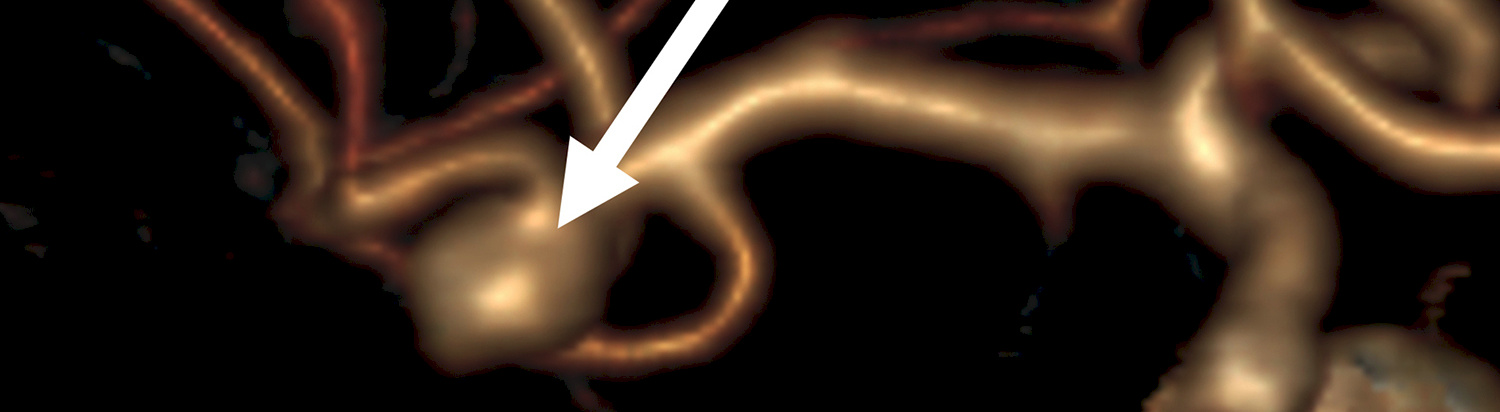

Lukinkalvonalaisen verenvuodon (SAV) aiheuttaa aivovaltimon pullistuman, aneurysman, puhkeaminen. Aivovaltimon aneurysmia on arviolta noin 50 000 - 100 000 suomalaisella, mutta valtaosa niistä ei koskaan puhkea eikä aiheuta oireita. Jos pullistuma havaitaan ennen sen puhkeamista, se voidaan useimmiten hoitaa. Toistaiseksi ei kuitenkaan pystytä erottamaan repeämisvaarassa olevia aneurysmia niistä, jotka voisi turvallisesti jättää hoitamatta.

Helsingin yliopiston, yliopistollisen sairaalan ja THL:n tutkijoiden tekemä laaja väestöpohjainen tutkimus osoitti, että lukinkalvonalaisen verenvuodon esiintyminen vaihtelee poikkeuksellisen paljon – kahdeksasta 171:een 100 000 henkilövuotta kohti – sen mukaan, millainen riskitekijöiden ’taakka’ henkilöllä on. Erityisen korkea vuotoriski oli tupakoivilla naisilla, joilla oli korkea verenpaine: heillä riski sairastua SA-vuotoon on 20 kertaa suurempi kuin tupakoimattomilla miehillä, joiden verenpaine on matala.

– Jos tupakoimattomalta mieheltä, jonka verenpaine on matala, diagnosoidaan vuotamaton aneurysma, sitä ei kenties ole aina tarpeen lähteä hoitamaan. Jos taas vuotamaton aneurysma diagnosoidaan tupakoivalta naiselta, jolla on kohonnut verenpaine, saattaa sen hoito useimmiten olla aiheellinen, Korja sanoo.